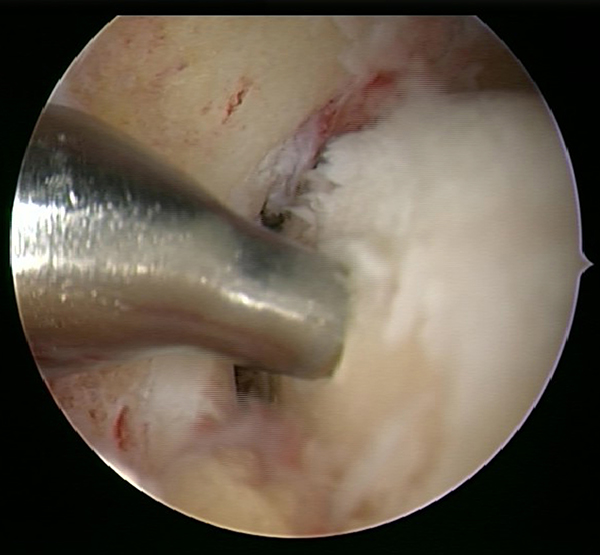

Ein aktuelles systematisches Review zur arthroskopisch-assistierten Frakturversorgung (AORIF) am Sprunggelenk identifizierte bei 495 von 782 Patienten (63,3%) chondrale Verletzungen 54. Weder durch die klinische Untersuchung noch mit konventionellen Röntgenaufnahmen oder mittels CT-Bildgebung lassen sich diese Verletzungen zuverlässig diagnostizieren. Aus diesem Grund rückt die arthroskopisch-assistierte Frakturversorgung am oberen Sprunggelenk zunehmend in den Fokus. Die Arthroskopie ermöglicht im Rahmen der Frakturversorgung sowohl die Kontrolle der Reposition als auch die Beurteilung und Therapie von intraartikulären Pathologien. Während sich die arthroskopisch-unterstützte Versorgung einiger Frakturen bereits etabliert hat (z.B. proximale Tibiafraktur) gehört der Einsatz der Arthroskopie bei der Frakturversorgung des oberen Sprunggelenks in den allermeisten Kliniken noch nicht zum Versorgungsalltag 155 Im Gegenteil, in einer aktuellen amerikanischen Datenbankanalyse des United Healthcare Orthopedic Datasets wurden zwischen 2007 und 2011 insgesamt 32 307 Patienten identifiziert, die mittels ORIF an einer Sprunggelenksfraktur versorgt wurden. In weniger als einem Prozent erfolgte eine arthroskopisch-assistierte Versorgung 55. Dem gegenüber stehen arthroskopische Studien der vergangenen Jahre, die zeigen konnten, wie häufig es zu intraartikulären Verletzungen bei Sprunggelenksfrakturen kommt. Das Risiko für diese intraartikulären Begleitverletzungen nimmt mit der Komplexität der Fraktur zu 5657. Es liegt also nahe, dass bei komplexeren Frakturen die Durchführung einer Arthroskopie im Rahmen der Frakturversorgung einen positiven Effekt auf das Behandlungsergebnis hat. Aus Sicht der Autoren sollte es Ziel für die Zukunft sein, die Frakturtypen zu identifizieren, die von einer arthroskopisch-assistierten Frakturversorgung profitieren. Die diagnostische Arthroskopie mit dem Ziel der gleichzeitigen arthroskopischen Therapie ist in der aktuellen S2-Leitlinie bereits eine Level-1b-Empfehlung. In den Abbildungen 20 – 30 ist schrittweise unser Vorgehen zur arthroskopisch assistierten Versorgung einer Trimalleolarfraktur dargestellt.

Intraartikuläre Begleitverletzungen